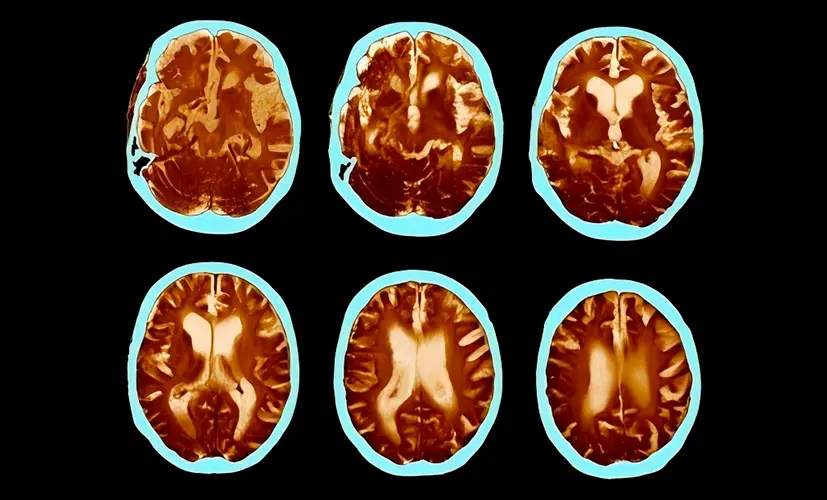

2. Dementia - the silent thief

Untreated cognitive decline can evolve into dementia. It may start as occasional forgetfulness, but before you know it, the condition has spread, impairing judgment and daily function. Patients describe the mental haze as a fog they can't escape. Most are diagnosed too late-when little more can be done.

4. Stroke caused by impaired blood flow

Cognitive decline is often the first sign of poor vascular health-not just in the brain. If ignored, a clot could strike, causing a stroke. I've seen seemingly healthy 45-year-old individuals on the operating table, fighting for their lives, all because they assumed their "lapses" were just a part of aging.

5. Nerve damage and mental confusion

Chronic cognitive decline can destroy the nerves responsible for mental processing and focus. Suddenly, you lose control over your thoughts. Mental disarray becomes your daily reality-even at a young age. People tell me they're too ashamed to engage with others. This isn't an "old person's condition"-it can happen to anyone.